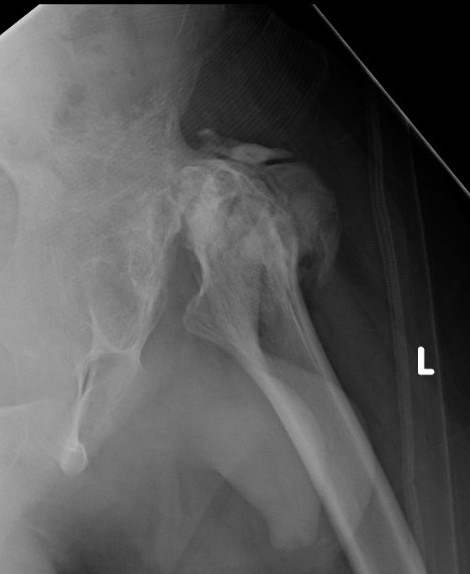

Septic arthritisSeptic arthritis

Advanced AVN and collapse after hip septic arthritis

Paed Hip OMPaed OM